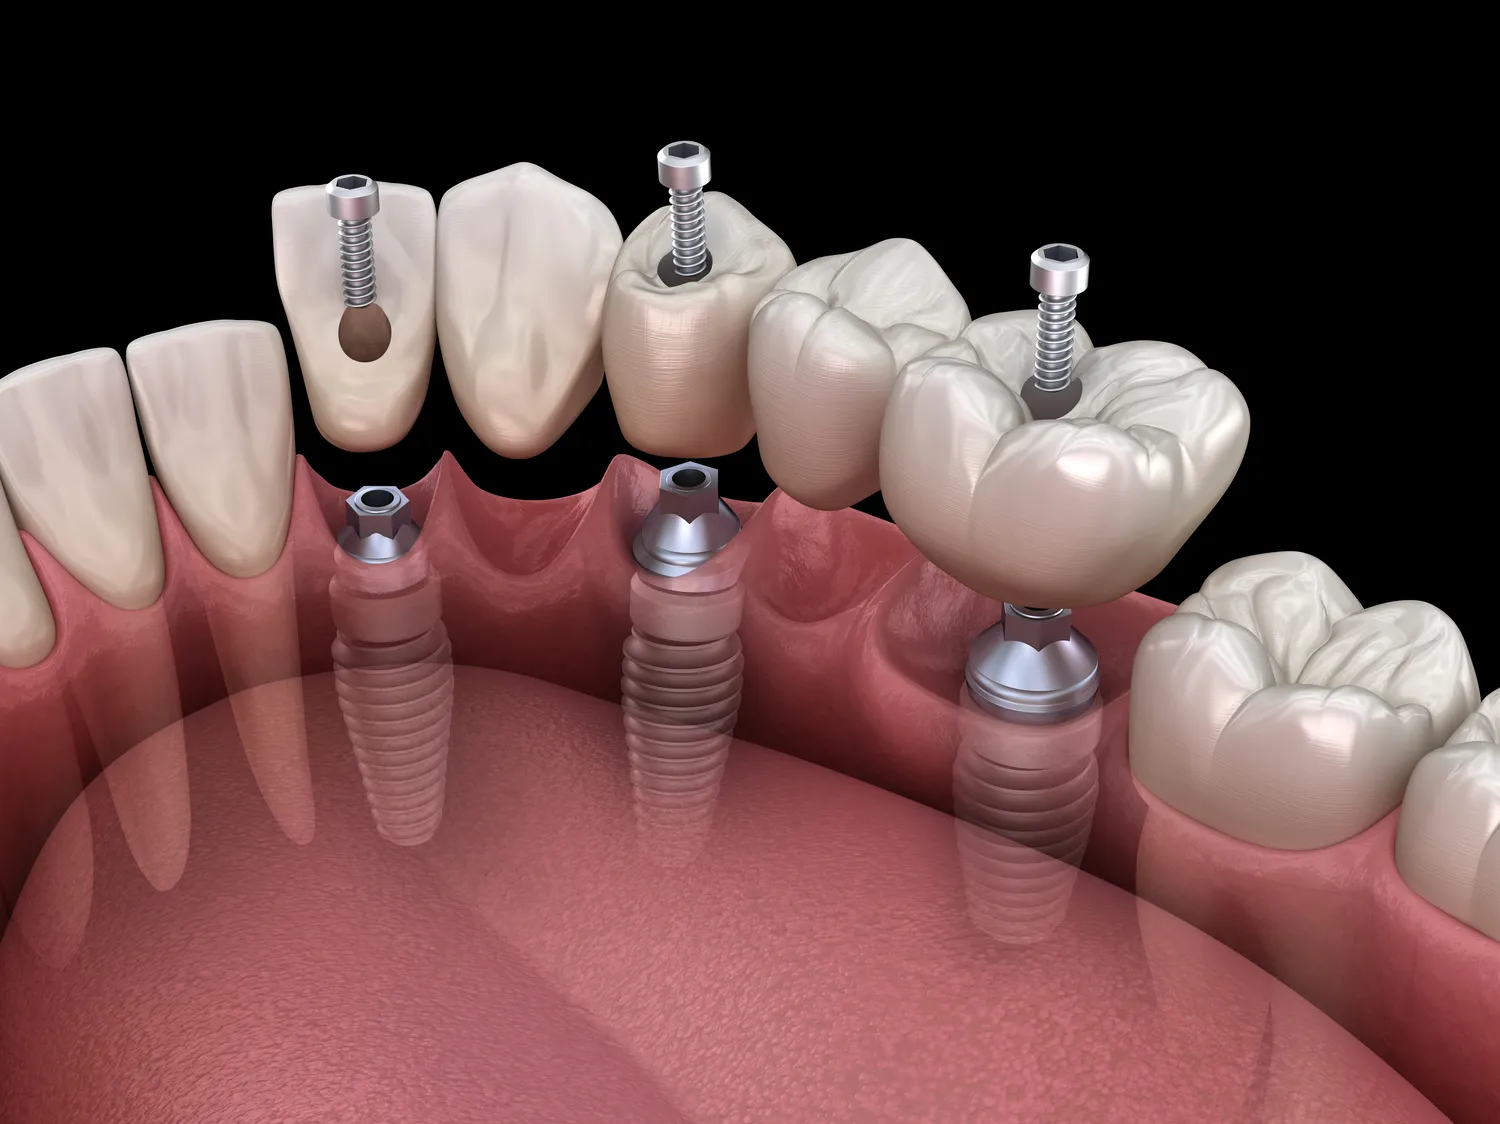

Proces zakupu implantów zębowych zaczyna się od wizyty u stomatologa, który przeprowadza szczegółową diagnostykę oraz ocenia stan zdrowia pacjenta. Na podstawie wyników badań lekarz może zaproponować odpowiedni plan leczenia oraz oszacować koszty związane z zabiegiem. Następnie pacjent powinien zapoznać się z różnymi ofertami klinik stomatologicznych oraz porównać ceny i opinie innych pacjentów. Po wyborze odpowiedniej placówki następuje etap przygotowania do zabiegu – może być konieczne wykonanie zdjęć rentgenowskich lub tomografii komputerowej w celu dokładnej analizy struktury kości szczęki. Po zakwalifikowaniu do zabiegu następuje jego realizacja – wszczepienie implantu odbywa się zazwyczaj w znieczuleniu miejscowym lub ogólnym, a czas trwania zabiegu zależy od liczby wszczepianych implantów oraz indywidualnych potrzeb pacjenta. Po zakończeniu zabiegu pacjent otrzymuje wskazówki dotyczące pielęgnacji oraz ewentualnych wizyt kontrolnych.

W ostatnich latach technologia w dziedzinie implantologii stomatologicznej znacznie się rozwinęła, co przyczyniło się do poprawy jakości leczenia oraz komfortu pacjentów. Jedną z najnowszych innowacji jest zastosowanie cyfrowych technologii w planowaniu zabiegów. Dzięki tomografii komputerowej oraz skanowaniu 3D lekarze mogą dokładnie ocenić stan kości oraz zaplanować precyzyjne umiejscowienie implantów. To pozwala na minimalizację ryzyka powikłań oraz skrócenie czasu gojenia. Kolejnym przełomem jest wykorzystanie materiałów biokompatybilnych, które sprzyjają integracji implantu z tkankami kostnymi pacjenta. Nowoczesne implanty często mają specjalne powłoki, które zwiększają ich przyczepność do kości. Warto również zwrócić uwagę na rozwój technik minimalnie inwazyjnych, które pozwalają na przeprowadzenie zabiegu bez konieczności dużych nacięć chirurgicznych. Dzięki temu pacjenci odczuwają mniejszy ból oraz szybciej wracają do codziennych aktywności. Również zastosowanie technologii CAD/CAM w produkcji koron protetycznych umożliwia stworzenie idealnie dopasowanych uzupełnień, co znacząco wpływa na estetykę i funkcjonalność uzębienia.

Czas gojenia po wszczepieniu implantów zębowych może być różny w zależności od wielu czynników, takich jak ogólny stan zdrowia pacjenta, jakość kości czy liczba wszczepianych implantów. Zazwyczaj proces ten trwa od kilku tygodni do kilku miesięcy. W przypadku standardowych implantów czas gojenia wynosi zazwyczaj od 3 do 6 miesięcy. W tym czasie dochodzi do procesu osteointegracji, czyli zespolenia implantu z kością szczęki. Ważne jest, aby podczas tego okresu unikać nadmiernego obciążania implantu oraz przestrzegać zaleceń lekarza dotyczących diety i higieny jamy ustnej. U niektórych pacjentów może być konieczne wykonanie dodatkowych zabiegów przed wszczepieniem implantu, takich jak przeszczepy kości czy sinus lift, co może wydłużyć czas całego procesu leczenia. Po zakończeniu etapu gojenia można przystąpić do wykonania koron protetycznych na wszczepionych implantach, co zazwyczaj zajmuje dodatkowe kilka tygodni.